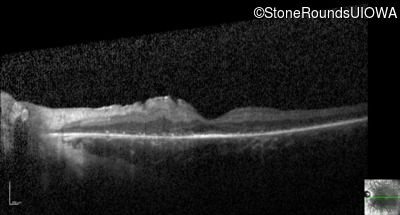

Optical Coherence Tomography - Right - 10/300

Exemplar / OCT Stack

OCT Stack